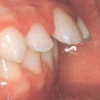

progeenne hambumus; alumised eeshambad on ettepoole ülemiste suhtes;